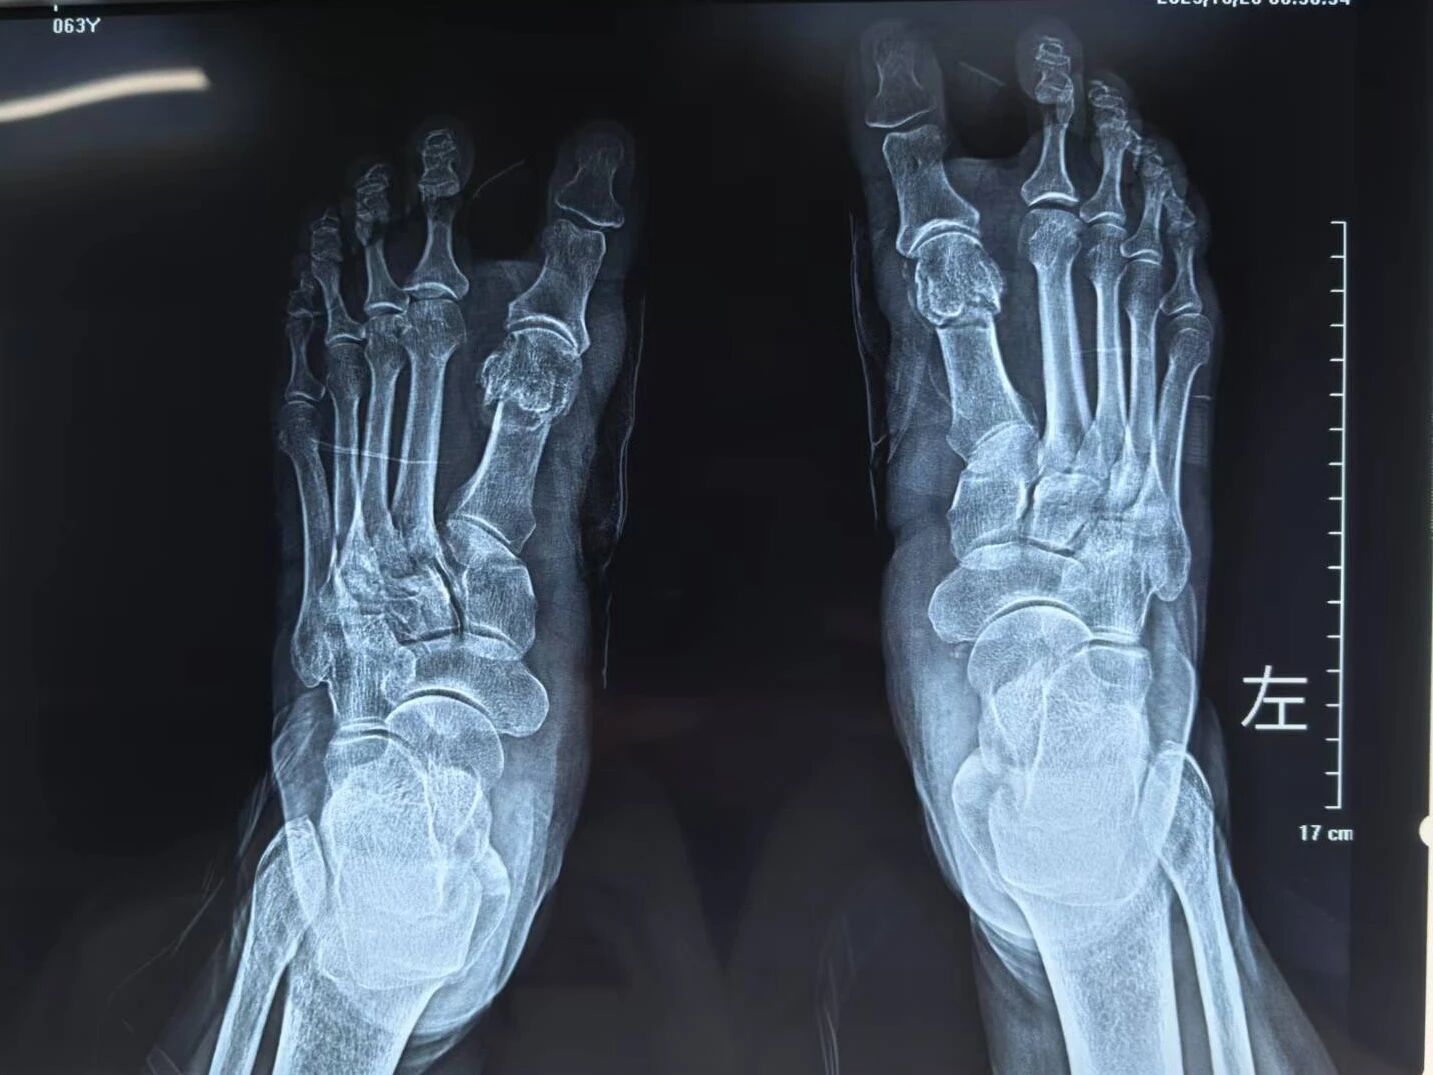

▲术后